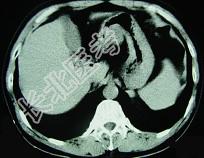

- 单项选择题男,52岁, 中上腹痛,影像检查如图, 最可能的诊断是  (    )

- A、慢性肥厚性胃炎

- B、胃癌

- C、胃溃疡

- D、胃平滑肌瘤

- E、胃平滑肌肉瘤